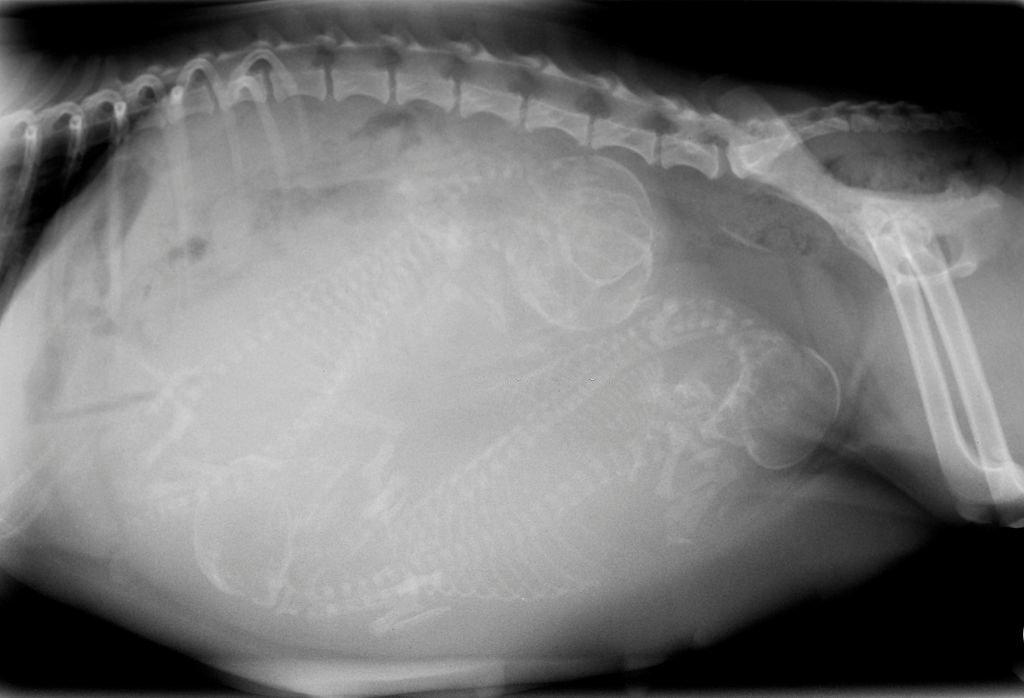

- Sinar-X: menggunakan x-ray sangat efektif untuk melihat apakah anjing hamil. Dengan x-ray juga bisa terlihat dengan jelas berapa jumlah janin anjing. Namun x-ray efektif untuk usia kehamilan di atas 55 hari..